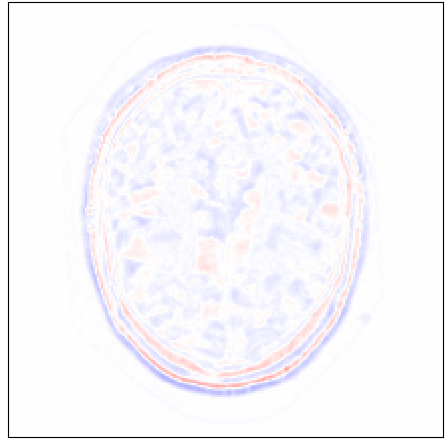

Figure 13: Comparing upsampling performance between cubic B-spline interpolation and proposed approach using T1-weighted adult brain MRI of the OASIS dataset. Original volumes with slice thickness and spacing of 1 mmtimes1millimeter1\text{\,}\mathrm{mm} were downsampled to 5 mmtimes5millimeter5\text{\,}\mathrm{mm} by applying a Gaussian blur before including every fifth slice in the test volume. Differences between reference (minuend) and synthesized slice (subtrahend). Blue corresponds to negative and red to positive differences. Image intensities are scaled to a [0,1]01[0,1] range. All difference images use the same color scale [1,1]11[-1,1].

Comparison With Conventional Interpolation Method: Qualitative comparison of generated axial brain MRI slices between cubic B-spline interpolation and proposed approach shown in Figure 13 reveals that the proposed method can synthesize excluded axial slices with higher image quality than conventional interpolation method. Moreover, visual inspection of coronal and sagittal slices shown in Figure 13 conveys that images generated by cubic B-spline interpolation more frequently suffer from aliasing artifacts than images generated by our proposed method.

In line with results reported for cardiac cine and neonatal brain MRI in Sections VI-B and VI-C, respectively, quantitative evaluation in terms of SSIM, PSNR, and VIF depicted in Figure 14 corroborate the qualitative findings. Measures were computed on sagittal slices through volume. The proposed method outperformed cubic B-spline interpolation and the differences are statistically significant (p<0.0001𝑝0.0001p<0.0001) in terms of SSIM and PSNR for all upsampling factors (K{2,3,4,5,6}𝐾23456K\in\{2,3,4,5,6\}).